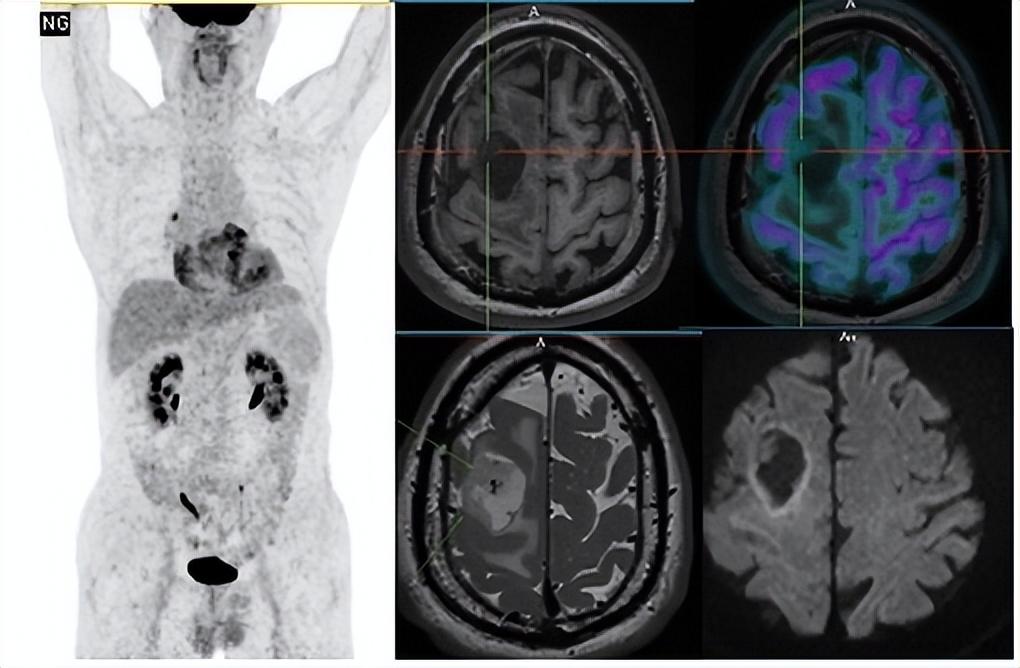

杨大爷(化名)因左侧肢体无力、晨起突发意识不清来到大医一院急诊就诊。MR检查发现右侧额叶肿物,是肿瘤脑转移还是脑内原发肿瘤,一时间难以确定。由于这两种疾病治疗方法不同,临床医生建议行PET进行全身扫描,杨大爷随后来到核医学科检查。PET/MR提示除右额叶肿物,全身其他各部位未见恶性肿瘤征象,从而确定右额叶肿物为脑内原发肿瘤,核医学科医生结合肿物的PET及MR影像特点,考虑为胶质母细胞瘤。杨大爷在得到明确诊断后,立刻进行了手术治疗,术后恢复良好出院。